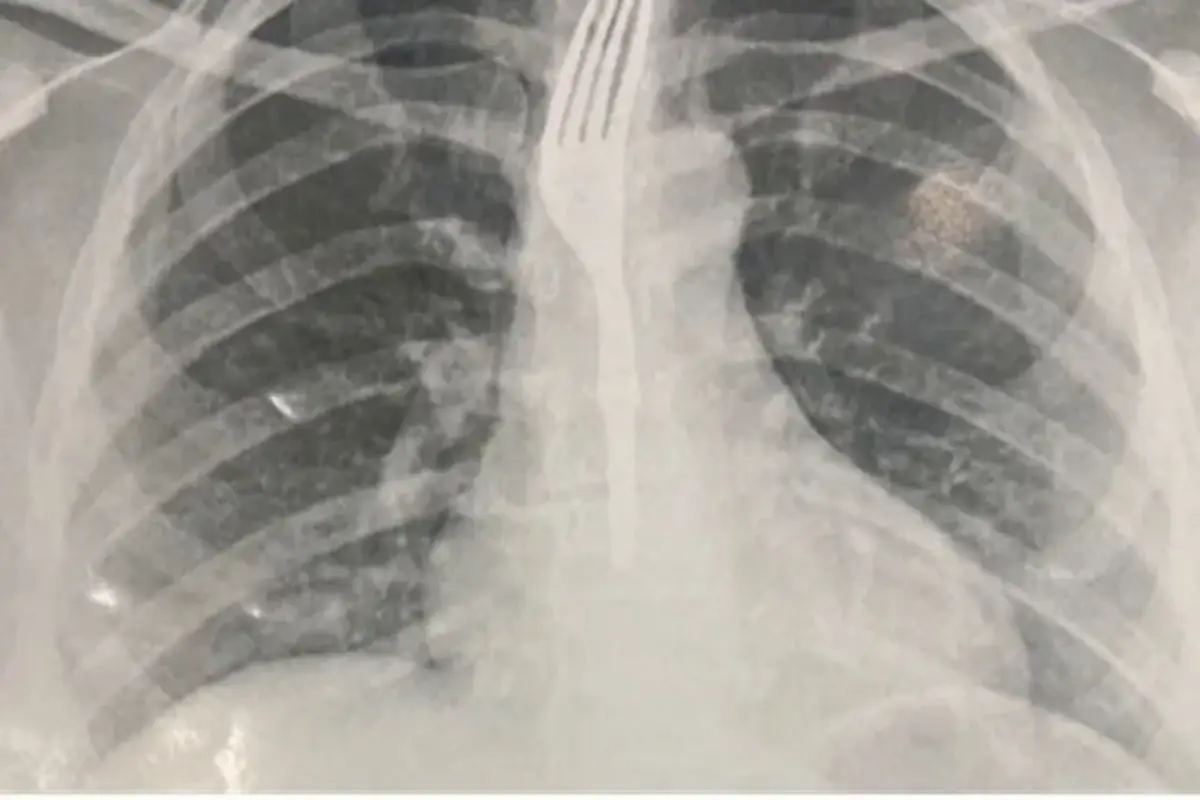

Segundo o site Achei Sudoeste, parceiro do Acorda Cidade, ela foi levada ao Hospital Geral de Guanambi (HGG), onde exames de imagem indicaram que o utensílio estava alojado no esôfago, em posição de risco.

Devido à gravidade do caso, os médicos decidiram transferir a paciente para Vitória da Conquista, onde será submetida a um procedimento especializado para a remoção do garfo.